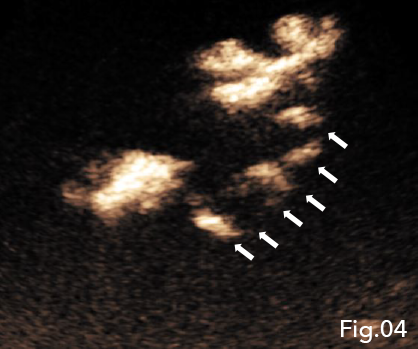

IV CEUS interrogation of the new second hypoechoic region superior to the primary abscess demonstrated features consistent with a hepatic abscess formation. IC CEUS demonstrated intracavitary communication between the two regions of abscess formation helping confirm the findings as a single abscess (Fig 4), negating the need for a second percutaneous hepatic drainage catheter. Furthermore the combination of IV and IC CEUS concluded that true fluid components were still present and the true size of the abscess cavity was much smaller than B-mode ultrasound had suggested (Fig 5).

Fig 4: IC CEUS demonstrating intracavitary communications (arrows) between the two abscess cavities helping confirm the findings as a single abscess